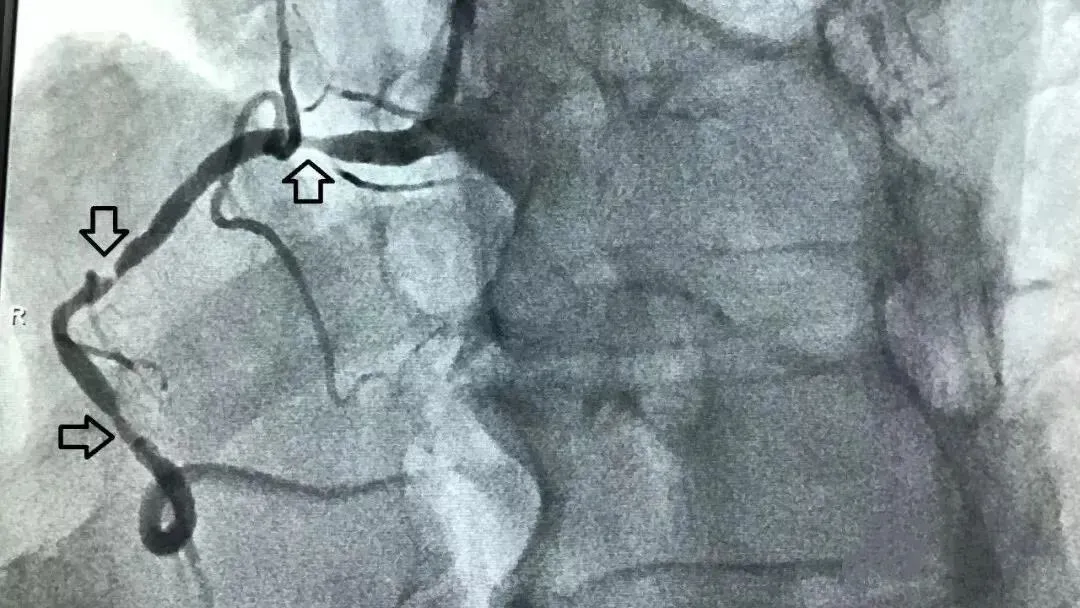

心脏冠状动脉堵塞99%医学示意图警惕!出现这些症状,就是心梗预警

文中的男子血管堵塞99%,几乎处于完全闭塞的状态,一旦登上飞机,在高空密闭环境下,一旦病情突发恶化,机上根本没有完善的急救条件,后果不堪设想。